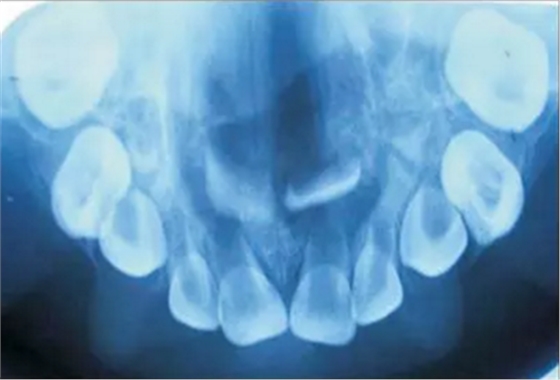

口內(nèi)咬合片可見(jiàn)上頜3×4cm大小低密度影,上頜中切牙恒牙胚移位。